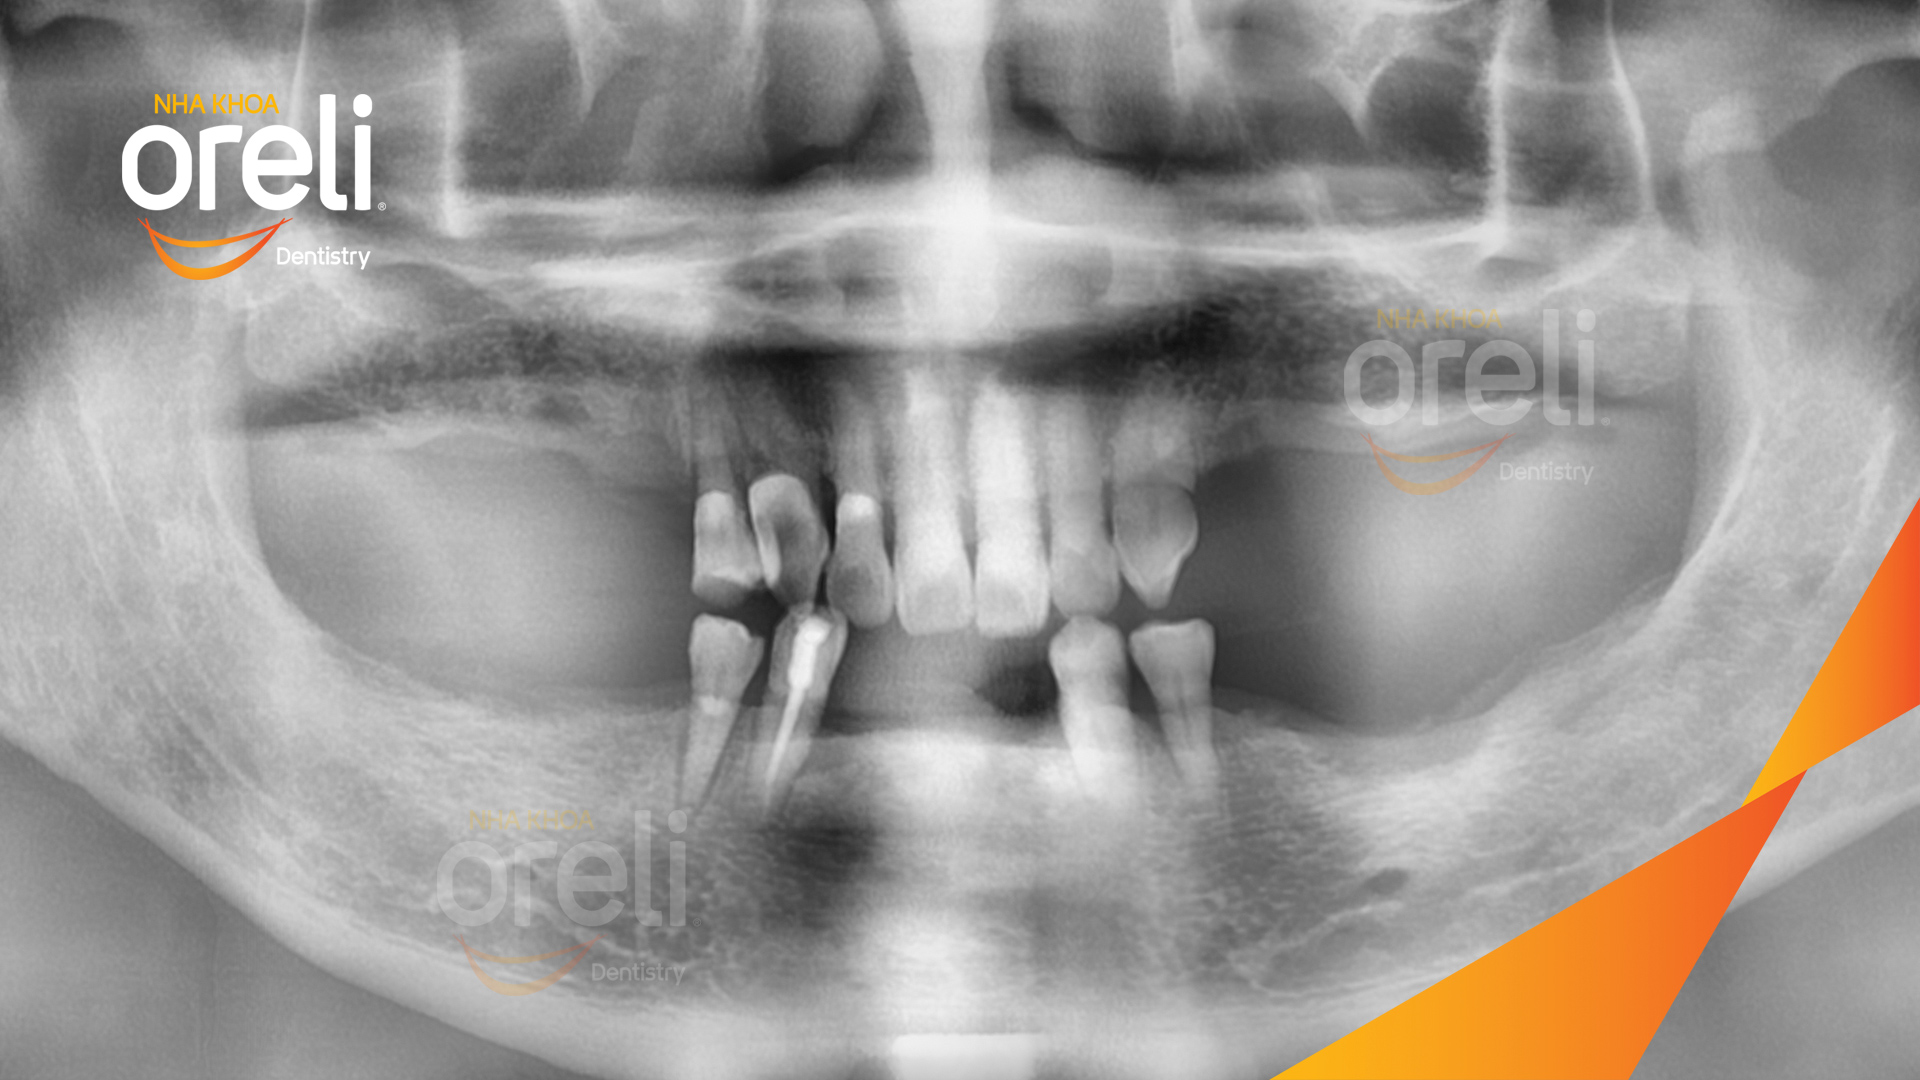

Tình trạng: Mất răng nhai vùng hàm trên và dưới

Giải pháp: Trồng răng implant toàn hàm dưới và vùng răng sau hàm trên

Hình ảnh thực tế